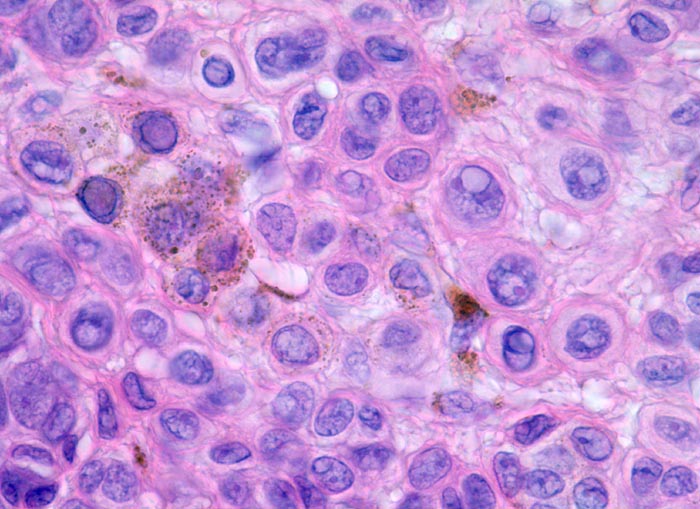

• Oberflächliche Tumorzellen enthalten teilweise körniges braunes Melaninpigment.

• Angrenzend an die pigmentierten Zellnester sind Melanophagen erkennbar, deren Zytplasma mit Melaningranula angefüllt sind.

• Die oberflächlichen Naevuszellen zeigen reichlich helles, teils pigmentiertes Zytoplasma und helle ovale Kerne mit kleinen, deutlich erkennbaren Nukleolen. Zur Tiefe hin werden die Naevuszellen kleiner, haben weniger Zytoplasma und dunkle kleine Kerne ohne gut erkennbaren Nucleolus. Die Zellnester werden zur Tiefe hin ebenfalls kleiner (=Ausreifung).

• Keine Mitosen, keine Zellatypien.